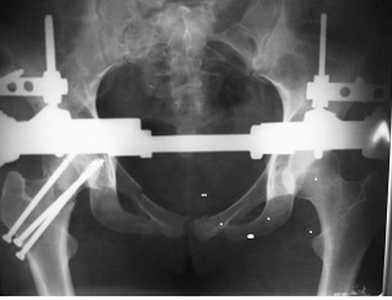

пока напрашивается следующий план

1 Подвздошный доступ две пластинки на крыло

2 простенький аппарат

3 после заживления стомы пластина на лоно

Уважаемый Александр, считаю что сейчас необходимо тазовое кольцо фиксировать АНФ- опорой таз+бедро, после компенсации состояния пациентки выполнить остеосинтез шейки бедра канюлированными винтами и выполнить полипроекционную Р-графию таза, а то не совсем понятен характер повреждения.

согласен, важно синтезировать шейку, стабилизировать таз передней рамой, потом к нему вернуться.

можно предполагать, что задний опорный комплекс пострадал минимально, таким образом передней рамой можно прицепиться к здоровой половине таза, тем самым создать относительную стабильность и дальше спокойно дообследовать пациента - КТ,inlet, Judet и т.д. Но сначала - синтез шейки.

Возможно и более изящное решение, наложить раздельно базы на крылья, на тракционном столе выполнить репозицию шейки, закрепить базы в таком положении, этого может хватить для таза.